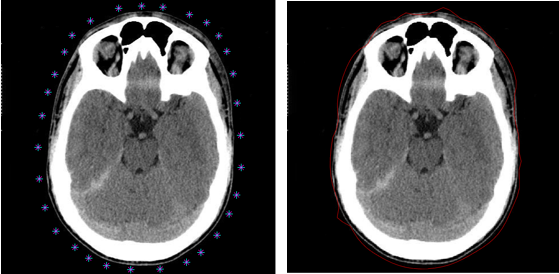

3.3实验结果 19

3.4本章小结 22